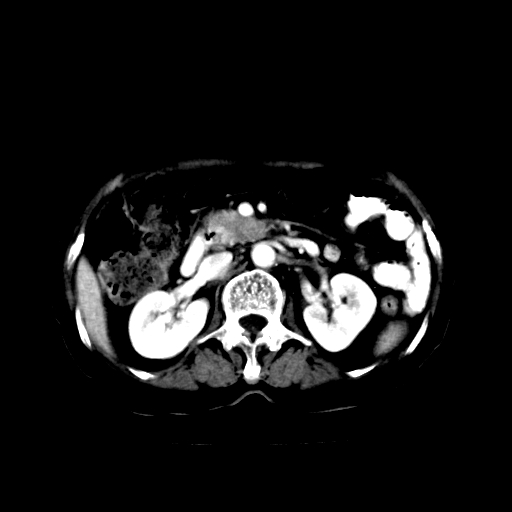

女,74岁,上腹部不适、腹胀两月余,黄染四天。请大家看看肿块周围血管情况。

肝内外胆管及胆囊扩张,胰管扩张,但“双管征”不明显,胆总管下段内见软组织有强化影,肠系膜上静脉推移不是很明显,考虑胆总管下段癌可能大。

胆囊胆总管扩张,胰头与十二指肠间似有一软组织密度灶,胰头增强不均,1壶腹癌,2胰头癌